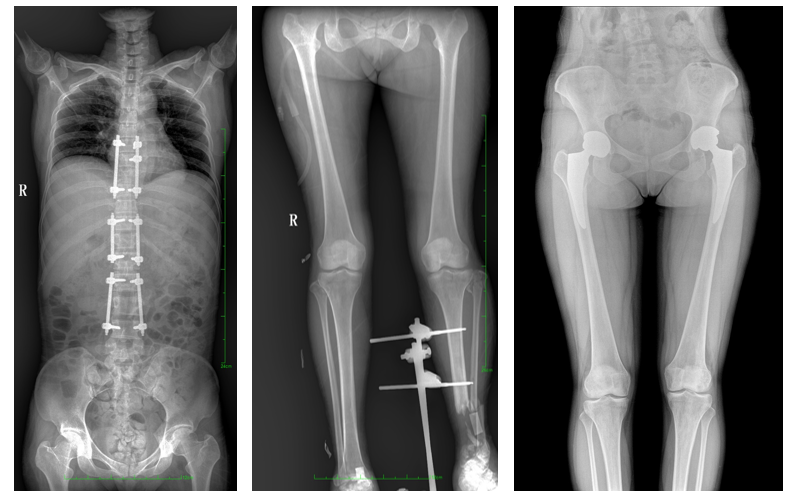

一、成像面積大。17"*34"有效視野,一次成像不拼接。相較于多張攝影再軟件拼接的DR設(shè)備,大視野平板動(dòng)態(tài)DR解決了拼接圖像存在密度不均勻,拼接處圖像配準(zhǔn)和放大效應(yīng)等問(wèn)題,給臨床帶來(lái)了大視野影像解決方案,可一次性覆蓋全脊柱或雙下肢影像。

如:全脊柱狀態(tài)評(píng)估、長(zhǎng)骨關(guān)節(jié)活動(dòng)度、下肢靜脈造影瓣膜功能評(píng)估、消化道功能評(píng)估、脊髓造影等更多大視野臨床應(yīng)用,多面手給醫(yī)生更多驚喜。

PLX8600大視野平板動(dòng)態(tài)DR可在低輻射劑量下獲得患者站立位、臥位的高質(zhì)量影像。搭載自主研發(fā)的圖像均衡處理系統(tǒng),能夠很好的均衡人體不同厚度組織的影像,視野大,圖像清晰,層次豐富。